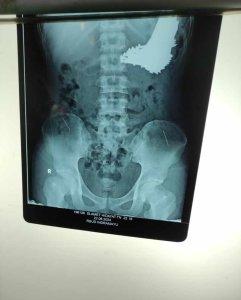

Paku yang berhasil diangkat tim bedah RSUD Indramayu dari lambung seorang pria.

Kejadian ini awalnya terungkap dari hasil pemeriksaan rontgen.

Foto rontgen itu memperlihatkan ada banyak paku berukuran besar yang bersarang di dalam lambung.

Sebanyak 70 batang paku yang bersarang di lambung pasien pun sudah berhasil diangkat.

“Total ada sebanyak 70 batang paku,” ujar dia.